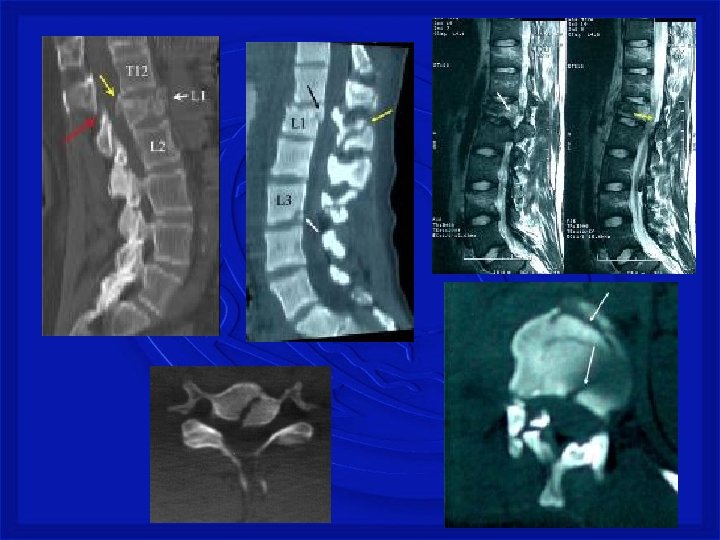

• TRAUMA FECHADO • Fratura Torácica • Rara devido proteção de caixa torácica • Tóraco Lombar • Comum. Quedas com impacto dos pés e região glútea • Lombar baixa • Os traumas produzem ruptura de discos

Mecanismo de Trauma Raqui. Medular com fratura As lesões ocorrem por: -Flexão, extensão, rotação, compressão por impacto axial ou combinação desses mecanismos.

FRATURA COMPRESSÃO TORÁCICA BAIXA

FRATURA COM LUXAÇÃO COMPLETA – TORÁCICA BAIXA

LESÕES - COLUNA